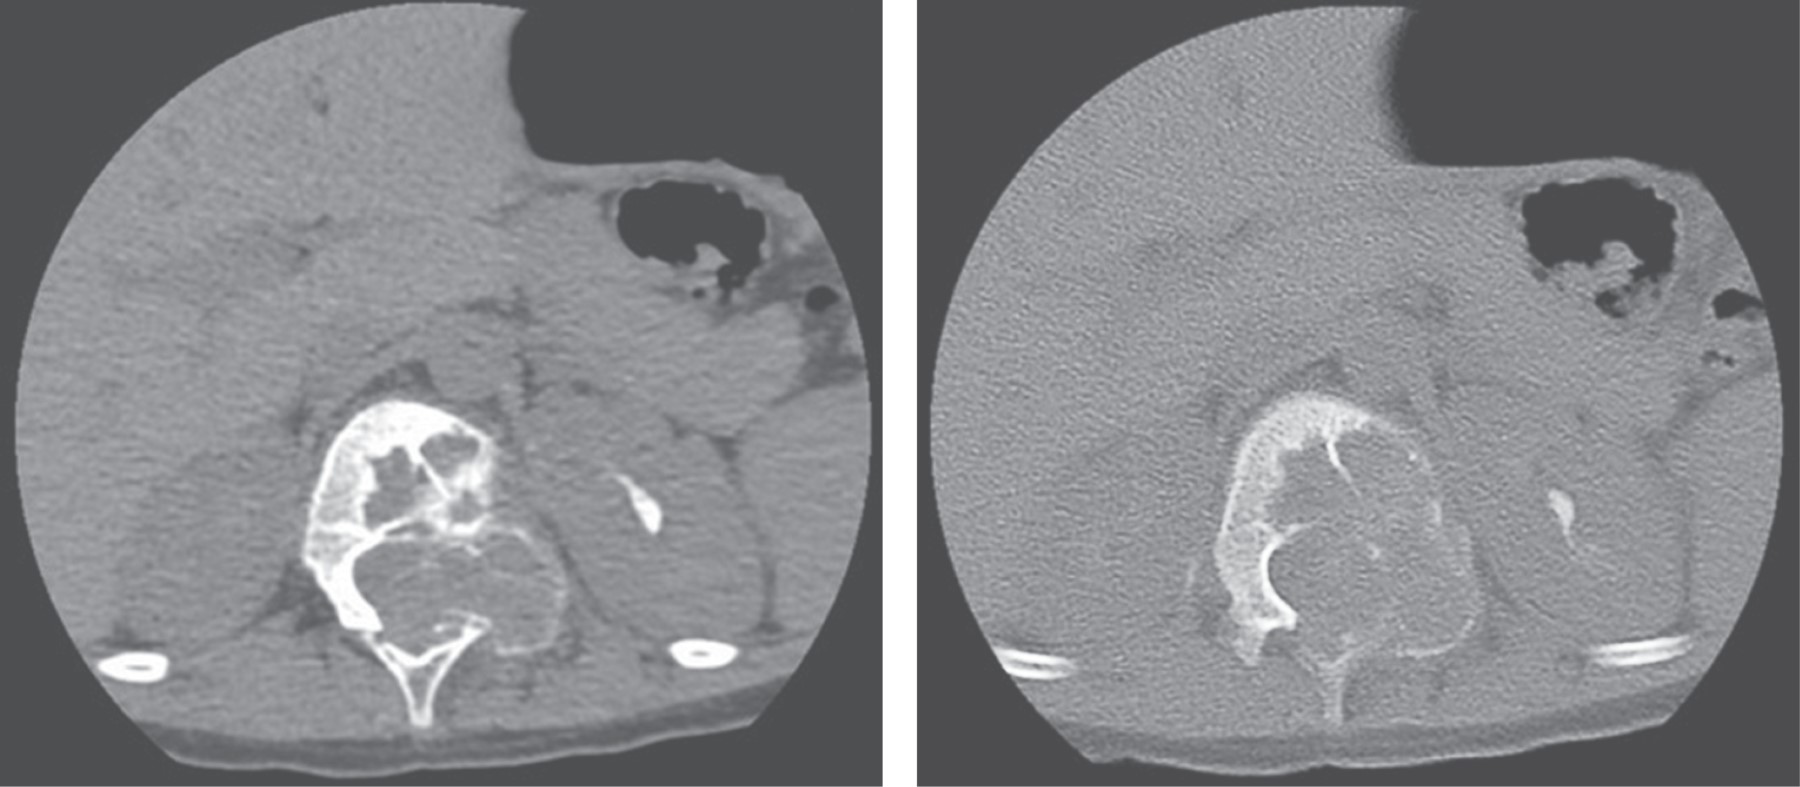

La tomografía toracolumbar mostró una lesión a nivel del cuerpo vertebral T12 y elementos posteriores de lado izquierdo de aspecto expansivo, lítico, con un interior trabeculado (Figura 1).